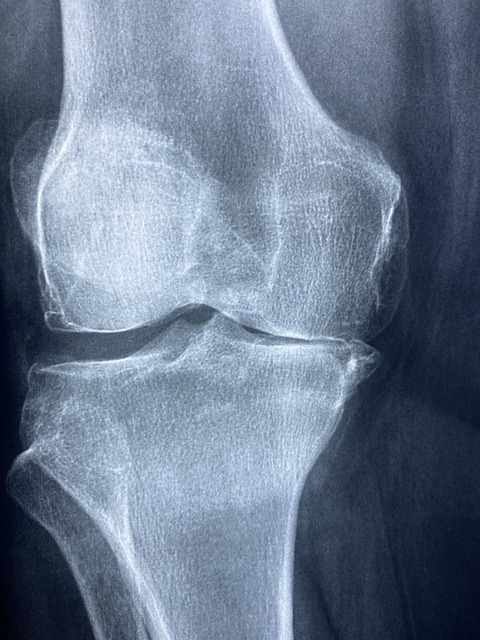

- 관절 통증 감소: 콘드로이친 효능으로 퇴행성 관절염 환자에게서 관절 통증을 줄이는 데 도움 됨이 있습니다. 이는 콘드로이친이 연골의 마모를 방지하고 염증을 줄이는 역할을 하기 때문입니다.

- 연골 보호 및 재생: 콘드로이친은 연골 세포의 생성을 촉진하고, 기존 연골을 보호하는 데 중요한 역할을 합니다. 이는 특히 나이가 들면서 발생하는 연골 손상을 예방하는 데 유용합니다.

- 염증 감소: 연구에 따르면 콘드로이친은 관절 내 염증을 감소시키는 데 효과적입니다. 이는 장기적으로 관절 건강을 유지하는 데 도움이 됩니다.

여러 연구에서 콘드로이친의 효능이 입증되었습니다. 예를 들어, 골관절염 환자를 대상으로 한 연구에서 콘드로이친이 관절 통증을 감소시키고, 연골 손상을 방지하는 효과가 있는 것으로 나타났습니다. 이러한 연구들은 콘드로이친의 장기적 사용이 안전하고 효과적임을 시사합니다.